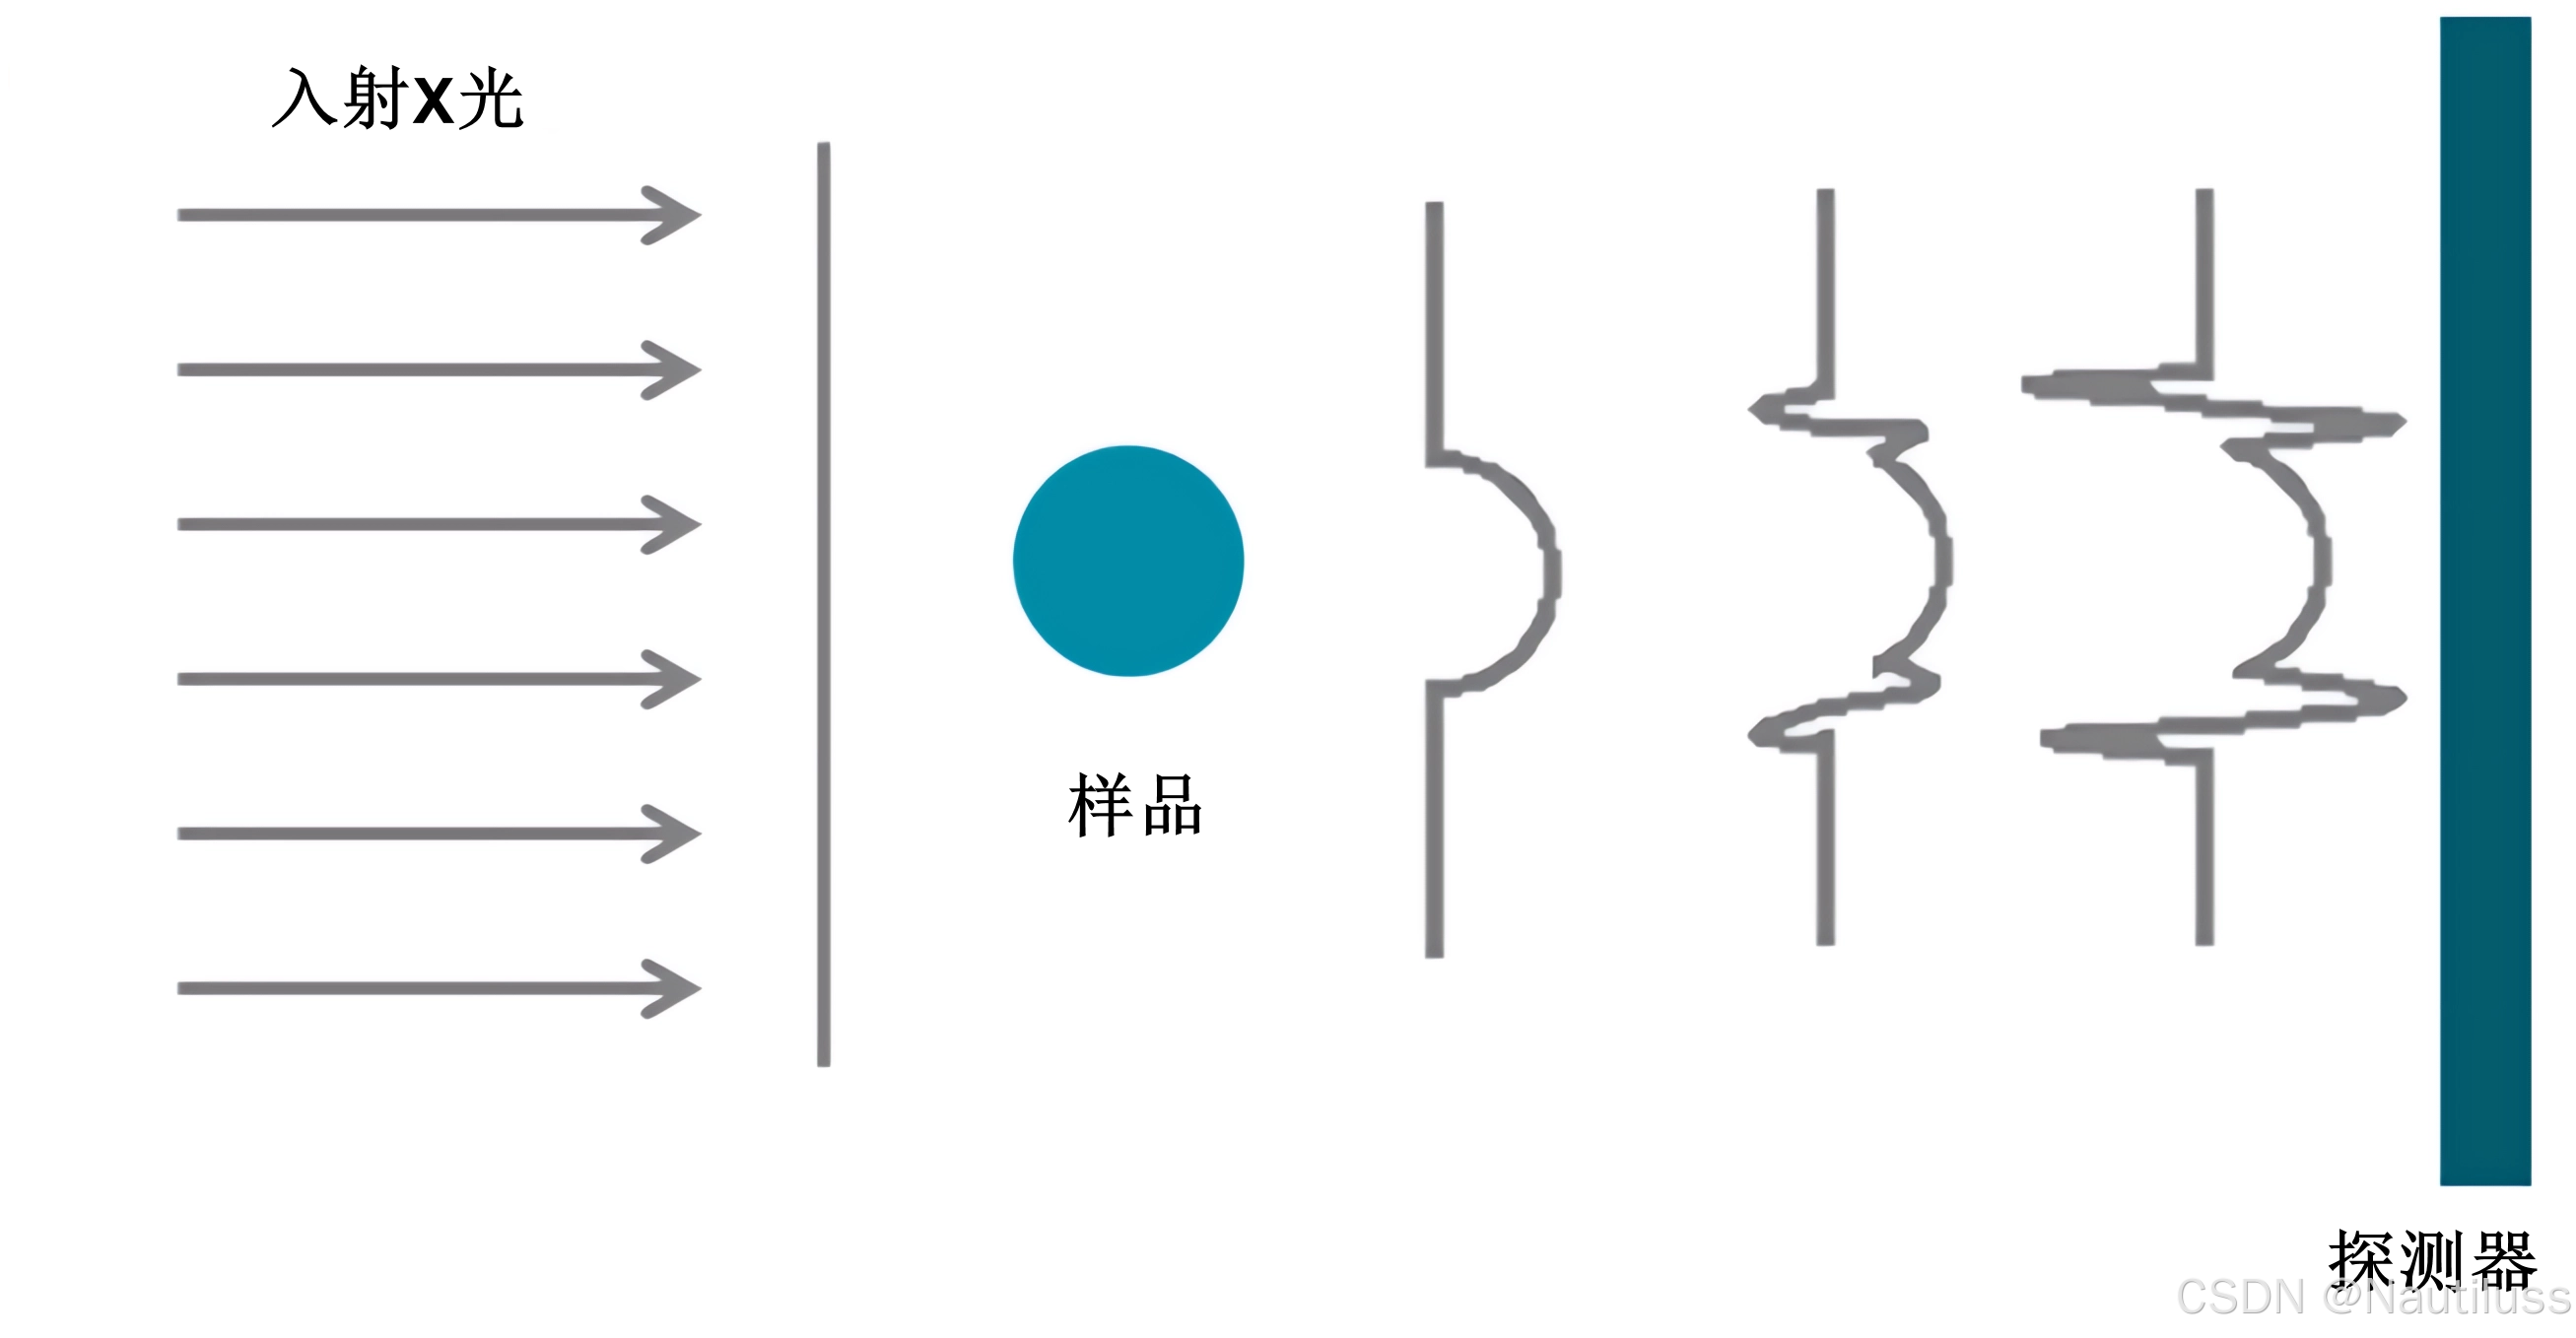

1、基于传播的成像(PBI)

基于传播的成像 (PBI)也称为 在线全息术、折射增强成像或相衬放射线照相术。该方法的实验设置与传统放射线照相术基本相同。它由串联布置的 X 射线源、样品和 X 射线探测器组成,不需要其他光学元件。唯一的区别是探测器不是直接放置在样品后面,而是放置在一定距离处,因此样品折射的辐射会干扰未变化的光束。这种简单的设置和较低的稳定性要求提供了该方法的一大优势,但该方法需要高亮度光源(由于与干涉测量方法相比,相干性要求较低,可以使用商业来源)。该方法仅需要源、物体和检测器,不需要其他设备。